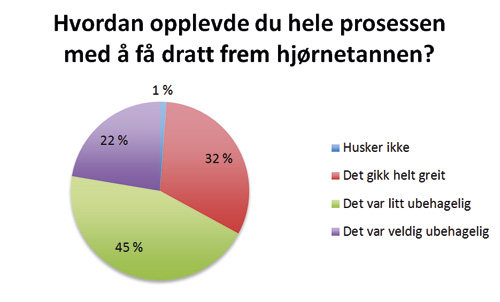

Hvordan opplevde du hele prosessen med å få dratt frem hjørnetannen?

Figur 4. Hvordan opplevde du hele prosessen med å få dratt frem hjørnetannen?

Den subjektive opplevelsen til pasientene etter behandling av palatinalt retinerte hjørnetenner ved lukket fremføring ble vurdert ut fra svarene fra spørreskjemaet som ble sendt til den enkelte pasient. Vi har ikke funnet noen tidligere studier hvor spørreskjema er benyttet i evaluering av denne type behandling. 90 % av pasientene var fornøyde med resultatet etter behandling. Vår studie viser også at pasientene stort sett er fornøyd uavhengig om pasienten har opplevd smerte under eller etter operasjonen. 20 % av pasientene som oppga at det var svært smertefullt under operasjonen oppga at de ikke var fornøyd med resultatet mot kun 4 % av dem som oppga noe smerter under operasjon. Blant de pasientene som synes at hele prosessen med å få dratt frem hjørnetann var veldig ubehagelig, er det overvekt av pasienter som er fornøyd med resultatet. At 39 av 47 pasientene var fornøyde selv om de svarte at de synes det tok lang tid, gjør at man kan anta at lang behandlingsperiode heller ikke er avgjørende for om pasienten blir fornøyd.

Ved økt fokus på smertekontroll, vil muligens færre pasienter føle at opplevelsen av hele prosessen var veldig ubehagelig, noe som hele 22 % svarte. Her må man ta i betraktning at «opplevelsen av hele prosessen» gjelder både den kirurgiske og kjeveortopediske delen av behandlingen. Vi ser i denne studien at det gjennomsnittlig tar 2 år fra frilegging av tann til debonding. Det at over halvparten av pasientene synes at behandlingen tok lang tid, er derfor ikke et overraskende resultat. Fremføring av en palatinalt retinert hjørnetann er en tidkrevende behandling, og man kan ikke risikere negativt utfall av behandlingen bare for å oppnå kortere behandlingsperiode for pasienten. Om pasientene synes behandlingen tok lenger tid enn det de i utgangspunktet forventet, er usikkert. Det er viktig at pasienten er innforstått med den lange behandlingstiden de har i vente. Muligens er ytterligere informasjon til pasient og foresatte angående den forventede behandlingstiden, nødvendig.